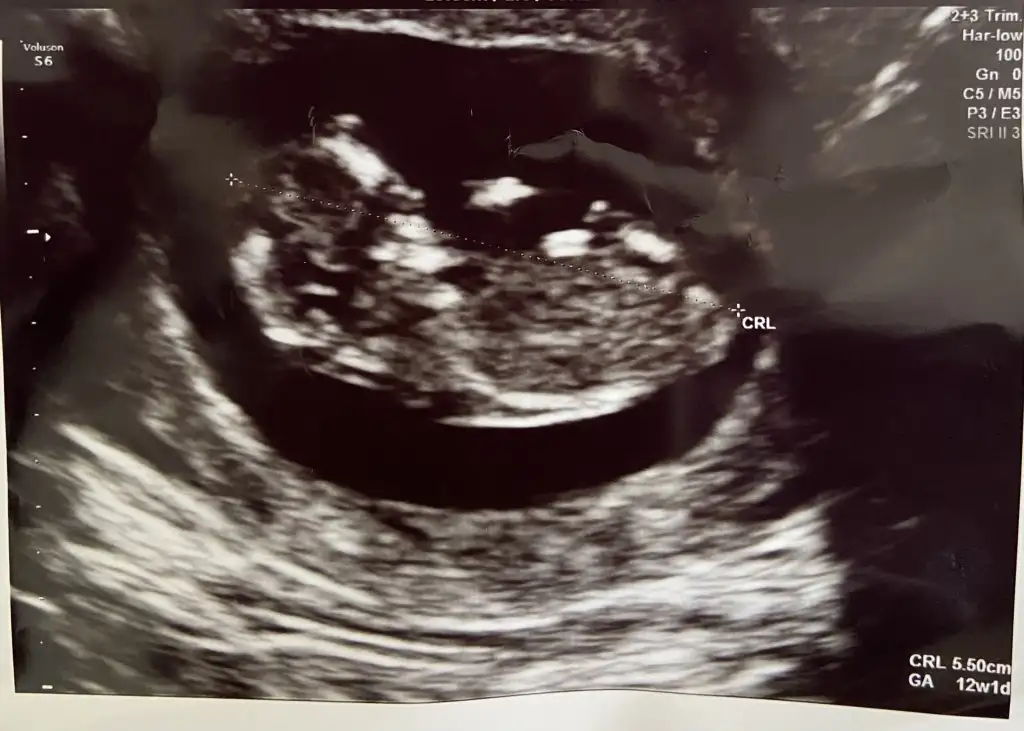

merhaba kaç haftalık görüntü acaba

11+1di sanırım o görüntü